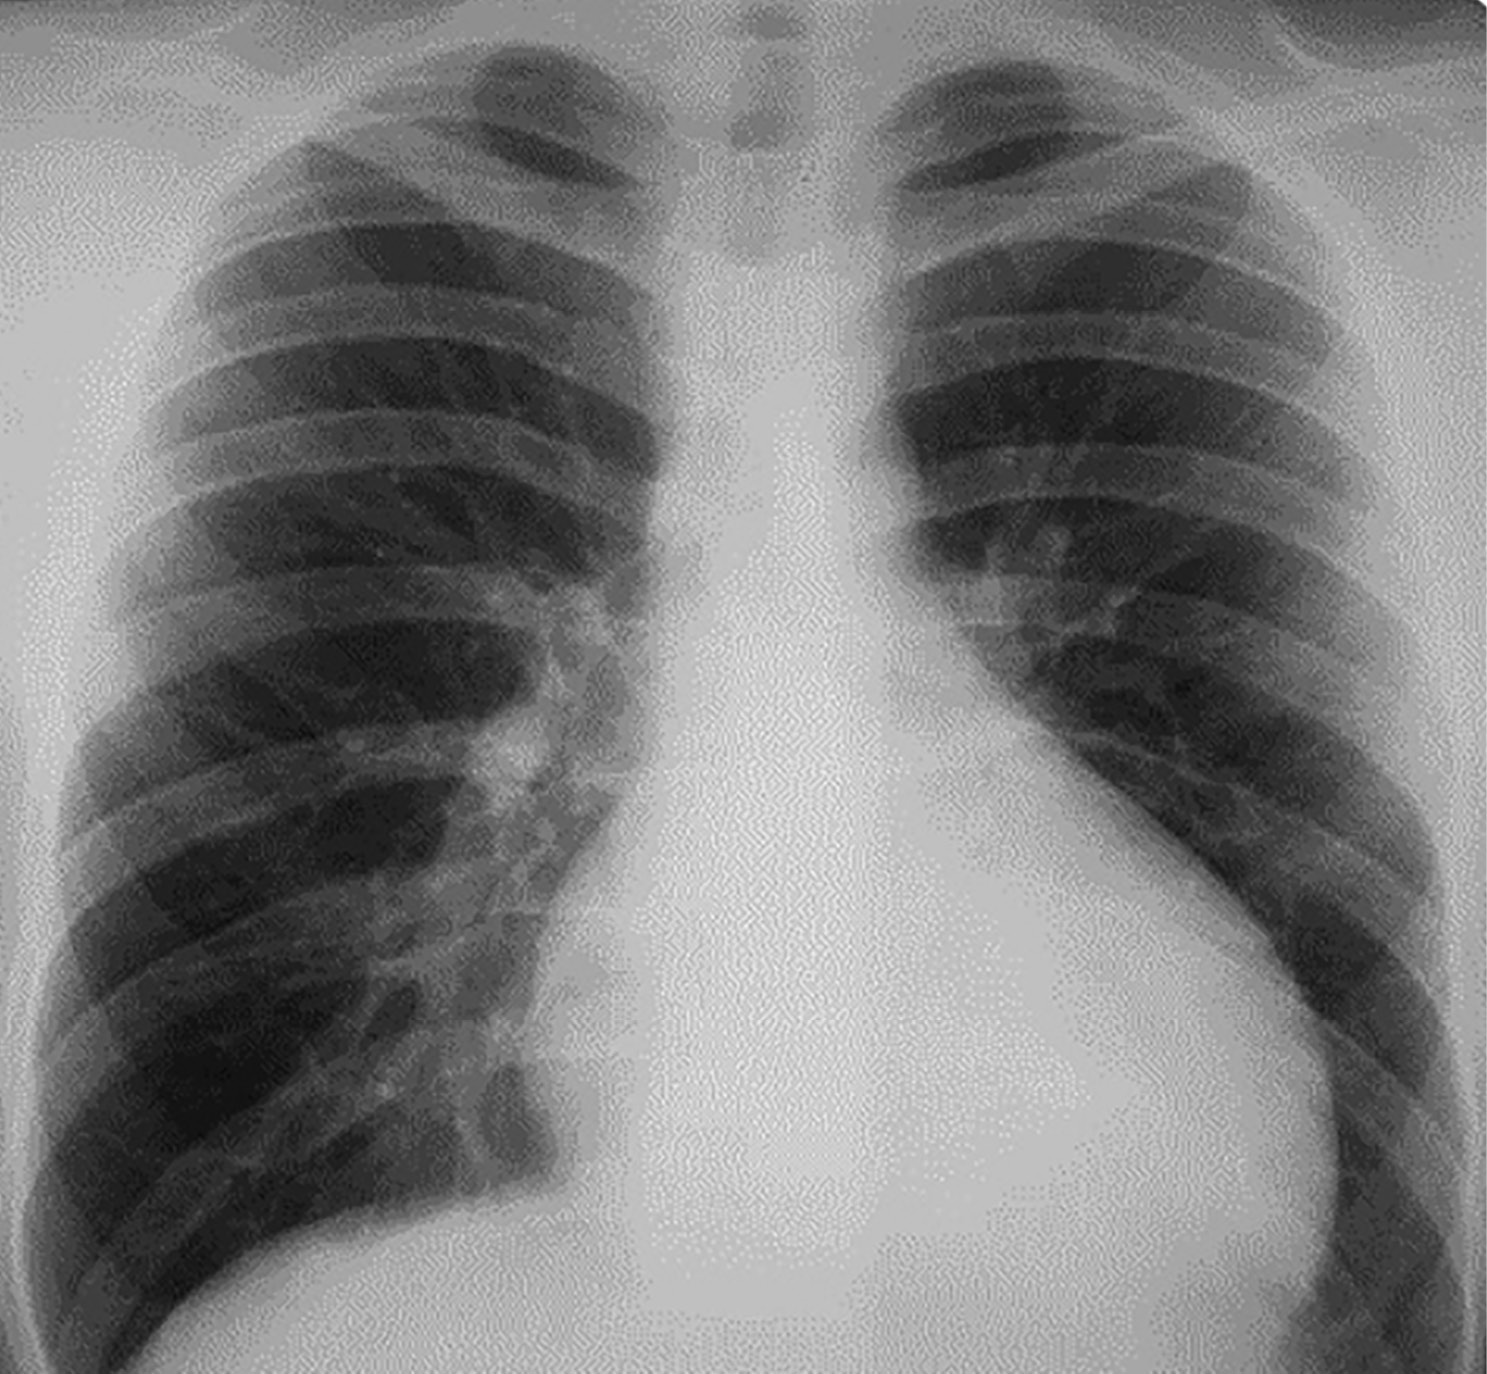

6. Рисунок 6 (а, б). Обзорные рентгенограммы органов грудной клетки в динамике. | |

Тема | ||

Тип | Исследовательские инструменты | |

Посмотреть

(266KB)

|

Метаданные ▾ |